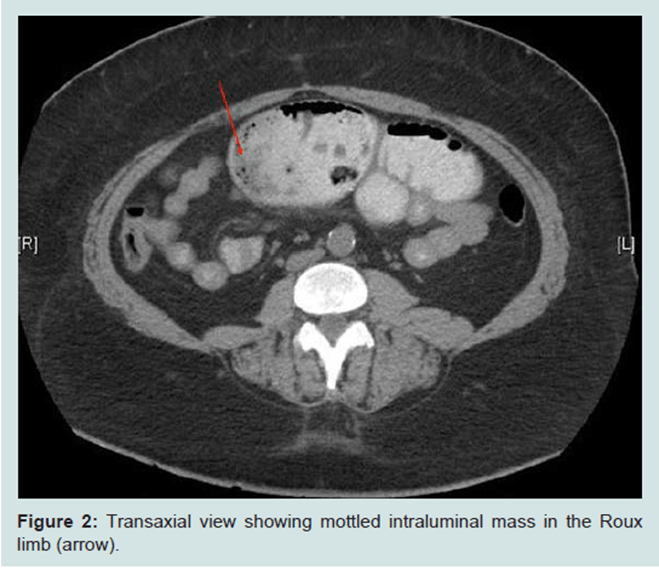

Obstruction may occur because of the narrowing of the lumen, where an ‘apple core’ lesion may appear, and possible large intraluminal mass may develop until advanced. This causes difficulty in understanding the difference between benign (early stage) and malignant (late stage) cancers (Khosla et al., 2022)

A CT scan of the small bowel – This can be difficult because it is in the middle area of the digestive tract.

CT findings differ and depend on the contrast agent.

Carcinomas of the duodenum: They are characterised by polypoidal (resembling polyps) and delineated lesions (clear boundaries).

Carcinomas of the jejunum and ileum: They are characterised by annular narrowing (ring-shaped narrowing), abrupt concentric (circles with a similar centre), irregular overhanging stenosis, which leads to partial or complete obstruction. Stenosis and stricture refer to the lumen of the intestine being narrowed (Khosla et al., 2022).